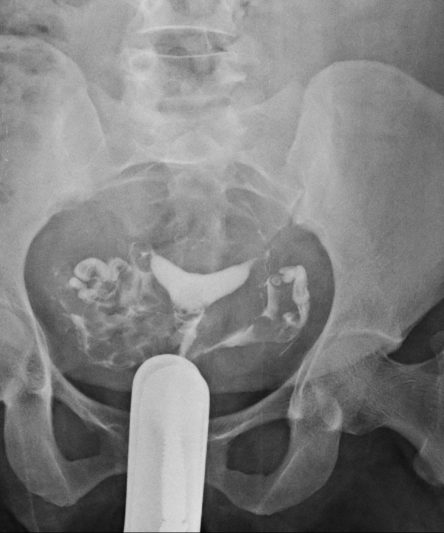

Microskan with Ultra high frequency can take the Lateral Lumbar Spine image of a 90 kg Patient with the correct image receptor